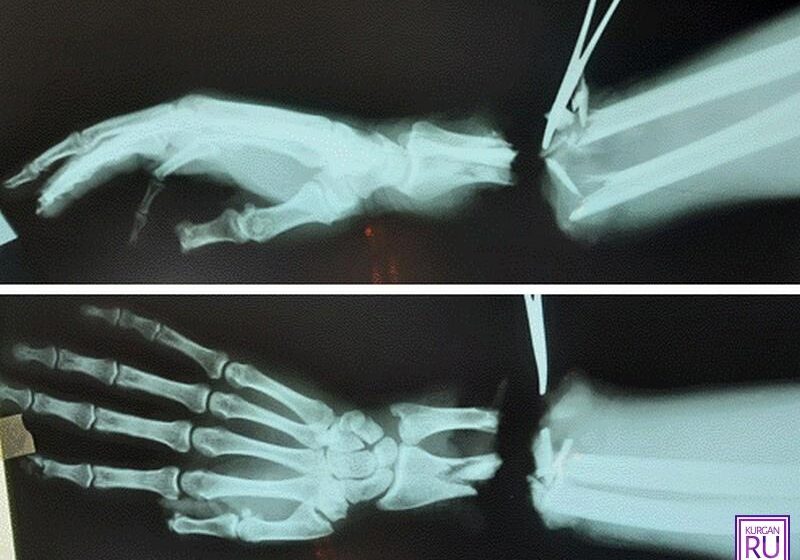

10 ноября. ПРАВМИР. Хирурги блестяще выполнили сложнейшую операцию по реплантации правой кисти пациента, сообщает Информационное агентство Курган.

Молодого мужчину доставили в Шадринскую ЦРБ с тяжелой производственной травмой — ему полностью оторвало кисть правой руки. Оказав пострадавшему первую помощь, медики приняли решение направить его в клинику реконструктивно-пластической хирургии и хирургии кисти Центра Илизарова.

Хирурги центра провели уникальную операцию, которая длилась целых семь часов. Им удалось сшить сосуды, поврежденные нервы и кости, восстановить кровообращение.

Реплантация кисти с применением микроскопа, микрохирургических инструментов и шовного материала тоньше человеческого волоса потребовала особых навыков от хирургов, — сообщает пресс-служба Центра Илизарова.

В результате у пациента произошло полное приживление кисти. На данный момент он проходит курс реабилитации и под контролем медиков выполняет специальную «зарядку» для руки, а также ходит на физиотерапию.

Через три недели после операции пациент смог активно сгибать и разгибать пальцы.